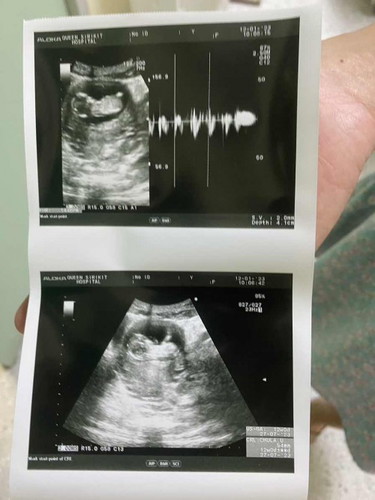

13 วีค น้องตัวเล็กไปมั้ยคะ

ถามหมอว่าน้องโตช้าไปมั้ย หมอบอกไม่ช้า ปกติดี แต่ในภาพคือดูไม่ค่อยออก ว่าน้องนอนหันหลังหรือเปล่า

เชื่อหมอค่ะแม่ อยากรู้ขนาดเทียบกับในแอปดูค่ะ 5.4 ซม ก็ไม่เล็กนะคะปกติ